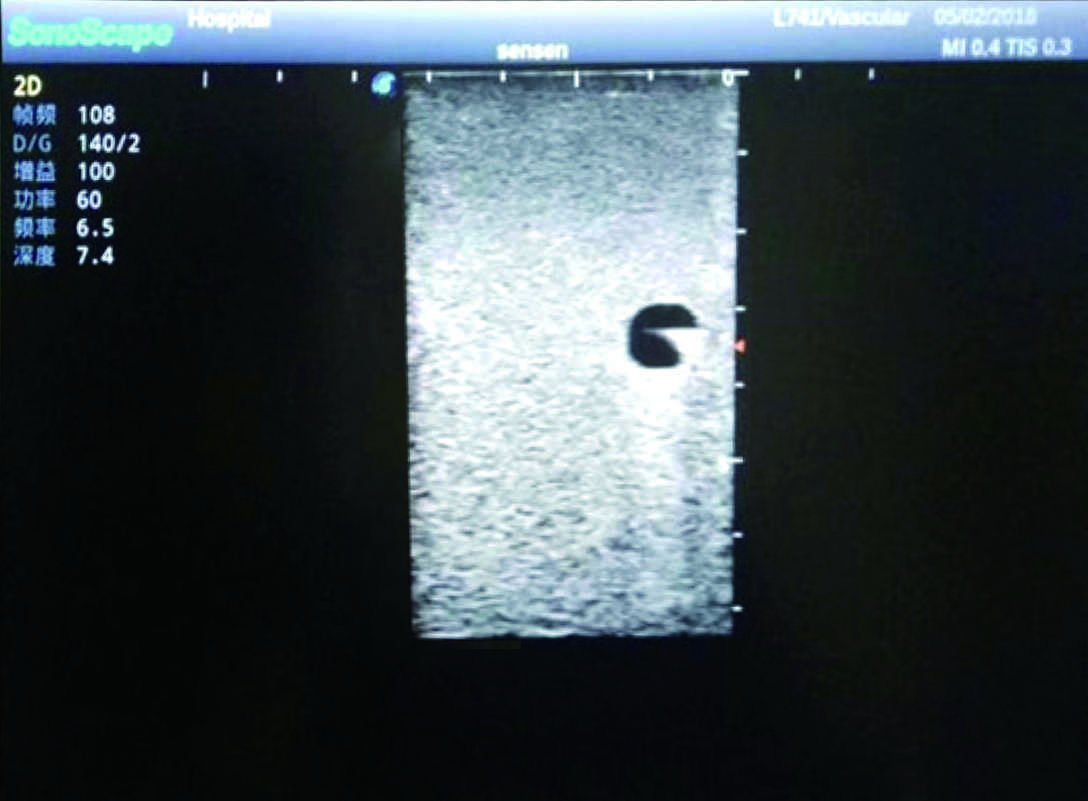

PICC Ultrasound Training Model

Model TYE1510.1

Outline

It is a model covering up from lobulus auriculae plane to the umbilical plane, and it has anatomical structures like clavicle, rib, sternocleidomastoid, jugular vein and basilic vein.

1)   Made of high molecular polymer ultrasound material, close to the real skin

2)   It can be used by real ultrasound machines

3)   Clear and real images of the tissues and organs (basilic vein and superior vena cava)

4)   When conducting vascular puncture, the piercing can be truly felt, and venous blood outflow can be seen